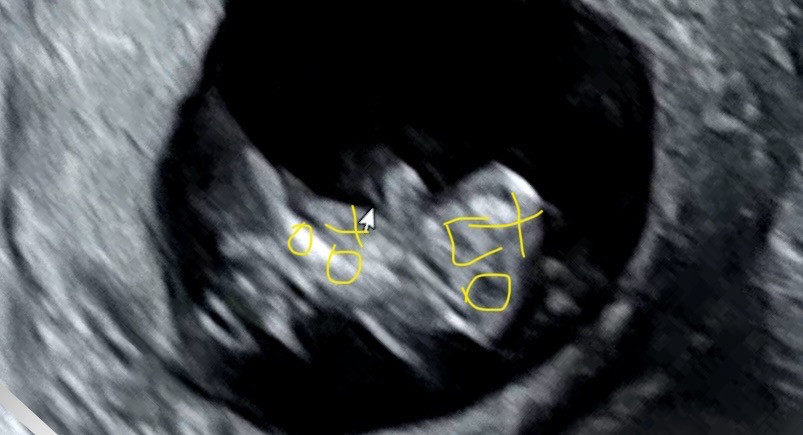

원래 남자아이 이렇게 잘 보이나요!

15주 0일 오늘 서브 병원에서 초음파로 성별 확인하고 왔는데 원래 남자애기들 초음파에서 이렇게 또렷하고 크게 보이는건가요ㅋㅋ 이 정도 보인거면 가족들에게 다 알려도 되겠죠? 초반엔 다리를 꼬고 있어서 선생님이 긴가민가 하시다가 거의 8분 정도 보고 확신에 차서 말씀해주시긴 했는데 인스타에서 성별 바뀐걸 자주봐서 고민이네욤

여자아기들은 아예 매끈매끈 해요 ㅋㅋ

저희집도 어제 확인했는데 저렇게 보여요...의사쌤이 잘 봤죠? 하고 말씀하셨어욬ㅋㅋ